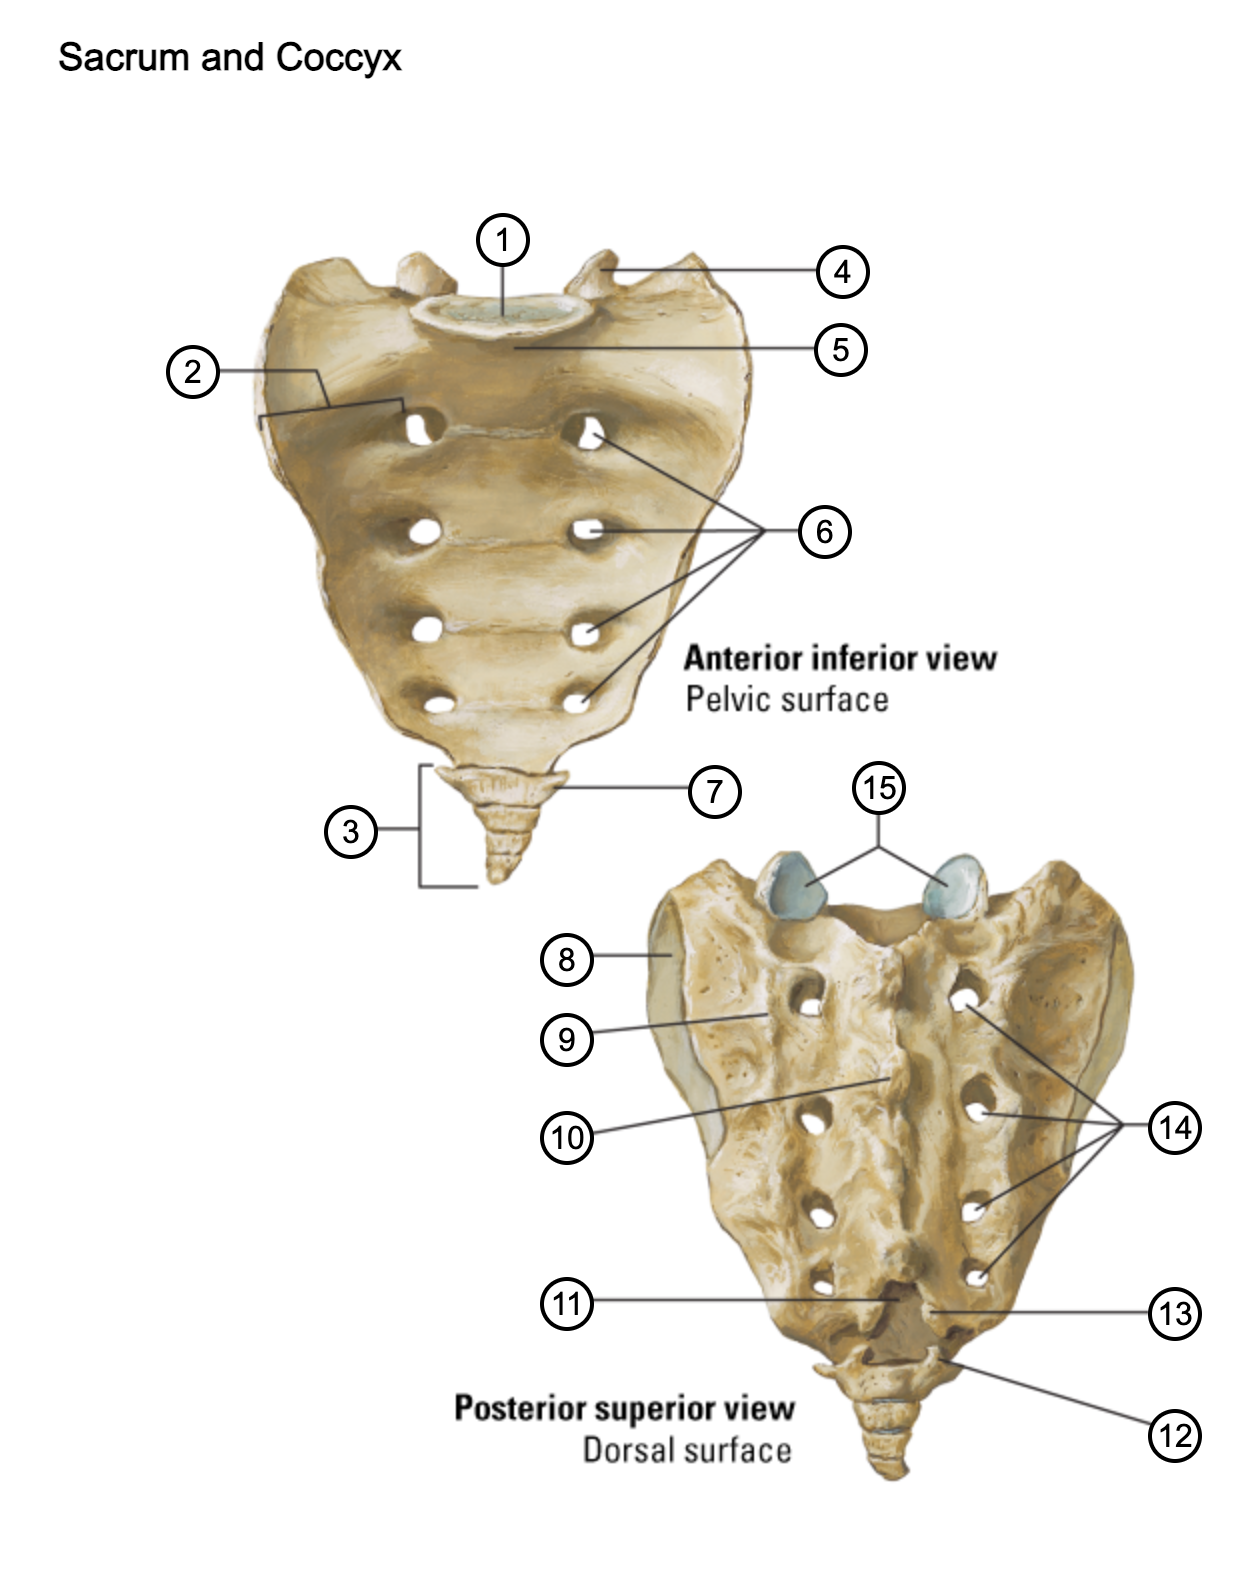

1

lumbosacral articular surface

2

ala of sacrum

3

coccyx

4

superior articular process

5

promontory

6

anterior sacral foramina

7

transverse process of coccyx

8

auricular surface

9

lateral sacral crest

10

median sacral crest

11

sacral hiatus

12

coccygeal horn

13

sacral horn

14

posterior sacral foramina

15

facets of superior articular processes